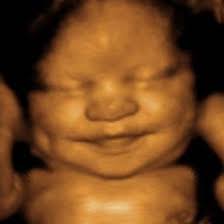

The Mississippi law that challenged Roe at the Supreme Court banned abortion at 15 weeks gestation. What is a pre-born baby doing at 15 weeks? Taste buds are being formed and nerves are connecting them to the brain. The baby’s legs are growing longer than her arms now. She can move all of her joints and limbs, and in fact she moves constantly. At 15 weeks, eyelids, eyebrows, eyelashes, nails, hair, and well-defined fingers and toes have already been formed.1 As I write this, people are rioting around our country because an unlegislated “right” to kill a baby was ruled unconstitutional–a baby who has been sucking his thumb for 3 weeks, and who can yawn, stretch, and make faces.

All pro-life people need to have these realities handy, and all pro-choice people need to read these undisputed facts of science and ask themselves honestly why they believe it is ok to purposefully kill a human being at any stage of gestation. Some may wave off prenatal science with the idea that pro-life people use it the same way some use creation science and don’t believe in the “Big Bang.” But all truth-seekers must admit that these facts are in a different category, out of the realm of scientific theory and into the realm of thumb-sucking actuality. I am pro-life because even if the Bible did not indisputably tell me so, the plain undisputed facts of science also tell me so.